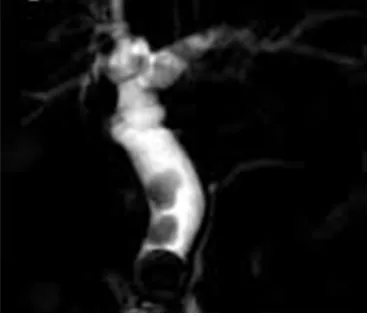

52세 여성이 오른쪽 상복부 통증으로 내원하였다. 혈압은 130/90 mmHg, 맥박은 82회/분, 호흡수는 16회/분, 체온은 38.7℃로 측정되었다. 혈액검사 결과 백혈구 수치는 16,500/mm3, 총빌리루빈 수치는 6.8mg/dL, ALP는 1250 U/L로 나타났다. 자기공명담도췌관조영술(MRCP) 사진이다. 치료는?

MRCP: CBD filling defect

• 오른쪽 상복부 통증, 황달, 발열 등 Charcot's triad와 함께 MRCP 상 CBD filling defect가 관찰되므로 CBD stone으로 인한 급성 담관염으로 진단할 수 있다.